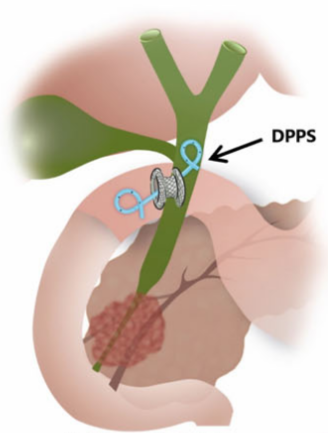

Een galwegontsteking kwam vaker voor na EUS-CDS daarom wordt er een extra stent door de nieuwe gemaakte verbinding geplaatst, hierdoor komt dit waarschijnlijk niet vaker voor dan na een ERCP (figuur 4). Deze stent wordt geplaatst tijdens dezelfde ingreep. Bij patiënten bij wie de dunne darm dichtzit is er een groter risico dat de stent verstopt raakt met het risico op een galwegontsteking. Indien voorafgaand of tijdens de procedure blijkt dat de dunne darm dichtzit dan wordt er om deze reden geen EUS-CDS verricht en zal een ERCP en als dat niet lukt een PTCD worden verricht.

Figuur 4. EUS-CDS met extra stent